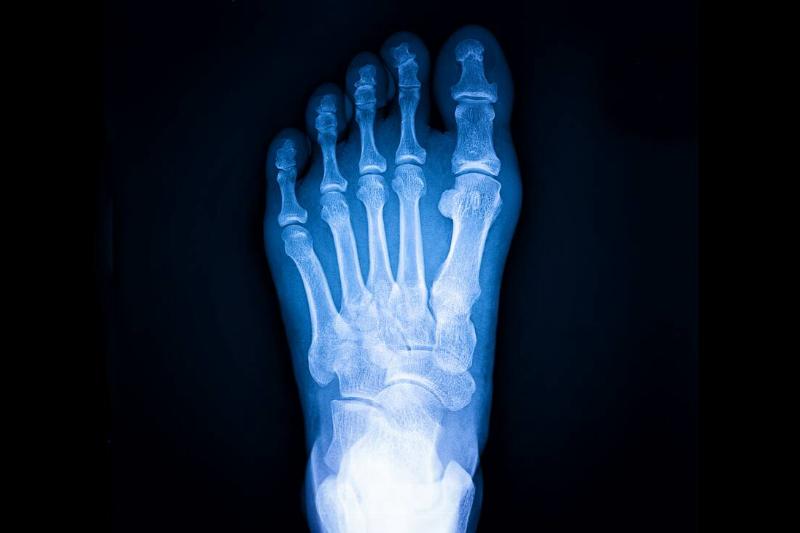

X-ray of foot.

Photo Credits: FoToArtist_1 / Envato Elements

Another painful condition manifested by pain when a particular spot on the leg or foot is pressed are tiny fractures in the bone referred to as stress fractures. Inattention to shin splints or overburdened muscles can cause the bone to absorb the shock. Again, walking too fast or too long before conditioning the muscles can be responsible.

Staying off the leg for at least six weeks and allowing the bone to heal before resuming walking will help. Gradually increasing speed and distance when returning to walking will help prevent pain and reduce any possibility of recurrence. Increasing calcium intake by eating calcium-rich foods or taking supplements can strengthen bones as well. Those over fifty will need more calcium than their younger counterparts.